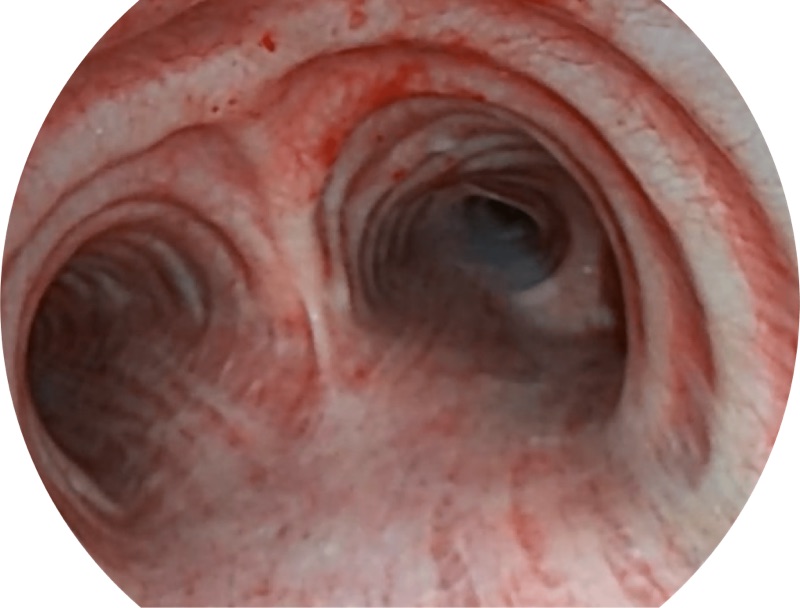

SFI